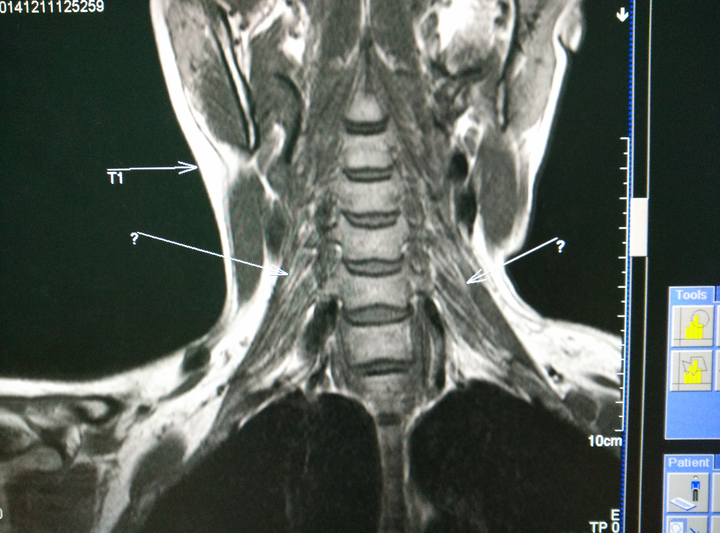

求大神指导臂丛神经磁共振扫描技术,顺便贴两张图?

磁共振颈椎神经压迫图

颈椎磁共振图片详解